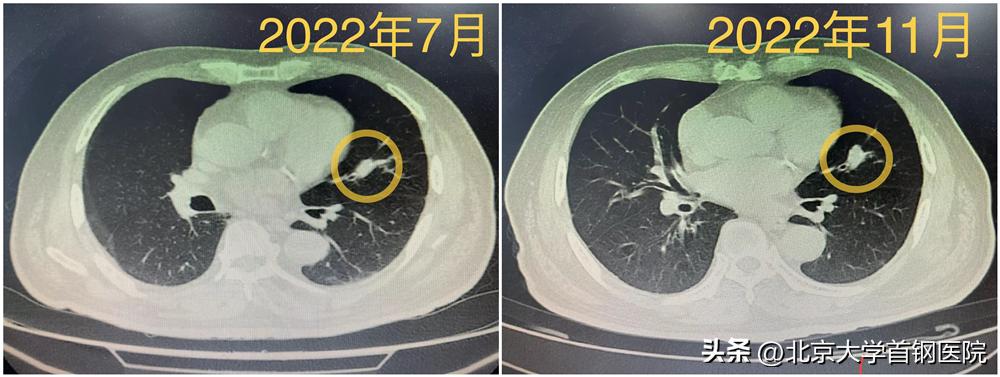

之所以请胸外科会诊,是因为在呼吸与危重症医学科住院期间,发现左肺上叶舌段实性结节,直径约1.5cm,CT显示较前缓慢增大,但是支气管镜的位置不合适,穿刺的风险又大,术前无法取到病理。